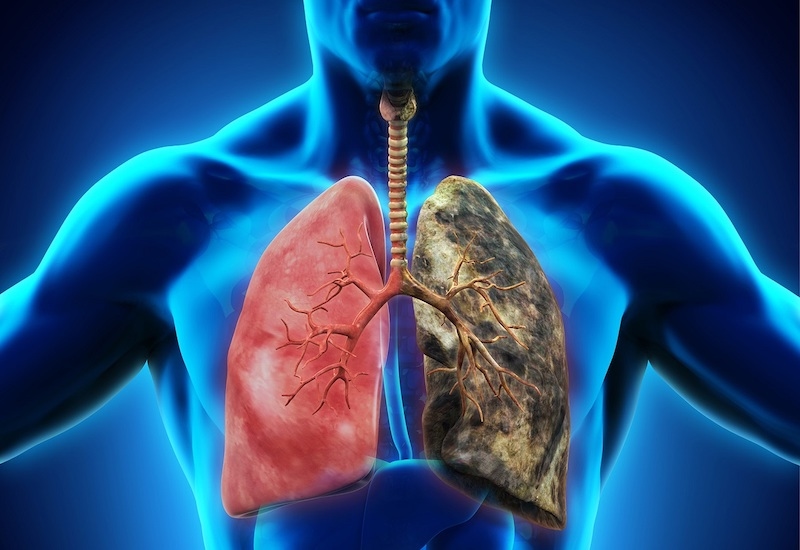

Đây là một bệnh lý ác tính xảy ra khi các tế bào bất thường trong phổi phát triển mất kiểm soát, hình thành khối u và có nguy cơ lan rộng sang các cơ quan khác. Quá trình này khởi phát từ các cấu trúc trong phổi như khí quản, phế quản, tiểu phế quản và phế nang – nơi diễn ra sự trao đổi oxy và carbon dioxide (CO2). Khi bệnh tiến triển, các tế bào ung thư có thể xâm lấn các mô lân cận hoặc di căn đến nhiều cơ quan trong cơ thể.

Ung thư phổi có thể xảy ra ở cả nam và nữ, với tỷ lệ mắc bệnh và tử vong khác nhau giữa các nhóm dân cư. Nguyên nhân hàng đầu gây bệnh là hút thuốc lá, bên cạnh đó còn có các yếu tố nguy cơ khác như tiếp xúc với hóa chất độc hại (radon, amiăng), ô nhiễm không khí và yếu tố di truyền.

Ung thư phổi là một bệnh lý ác tính xảy ra khi các tế bào bất thường trong phổi phát triển mất kiểm soát, hình thành khối u và có nguy cơ lan rộng sang các cơ quan khác